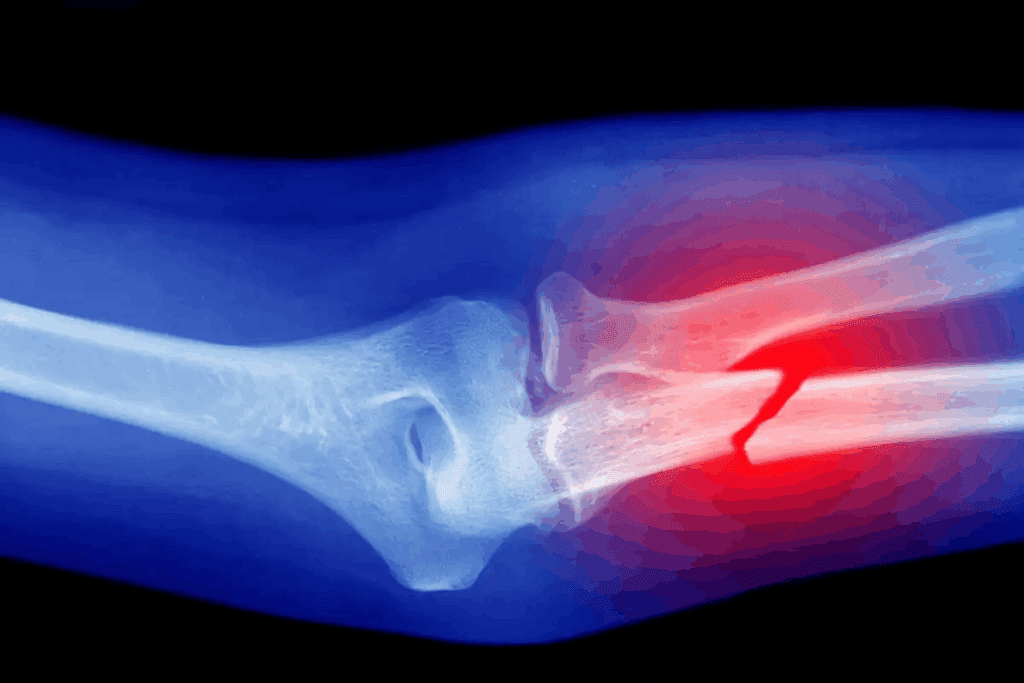

Displaced Fractures: Severe Pain

Displaced fractures have bone fragments out of place, leading to severe pain. The pain is intense because of the bone’s misalignment and damage to surrounding tissues.

Key features of pain from displaced fractures include:

- Sharp, intense pain at the time of injury

- Increased pain with any movement or attempt to use the affected limb

- Visible deformity or abnormal positioning of the affected area